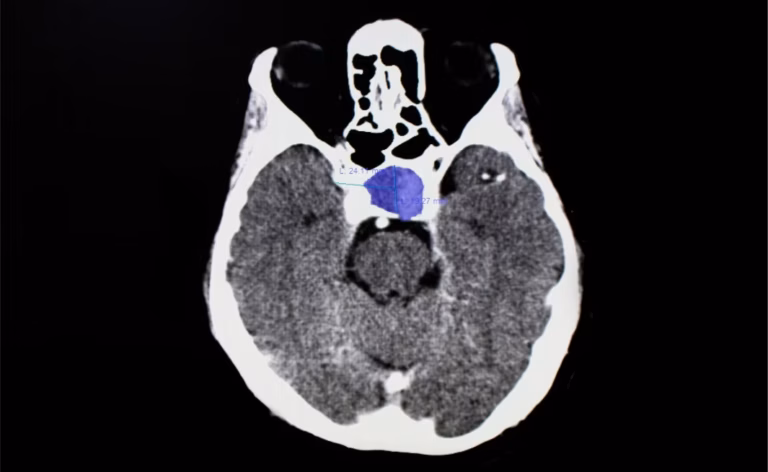

Oh my god, there were so many tests. I did a cat-scan and an MRI. Then, I had to go to have a Venus trapping which is when they put tubes from my groin all the way to my brain. After all the tests, the specialist diagnosed me.

I had a pituitary tumor that was at the base of the brain, touching the optic nerve. It was about the size of an orange. The doctors said that another month I would have been blind in one eye.